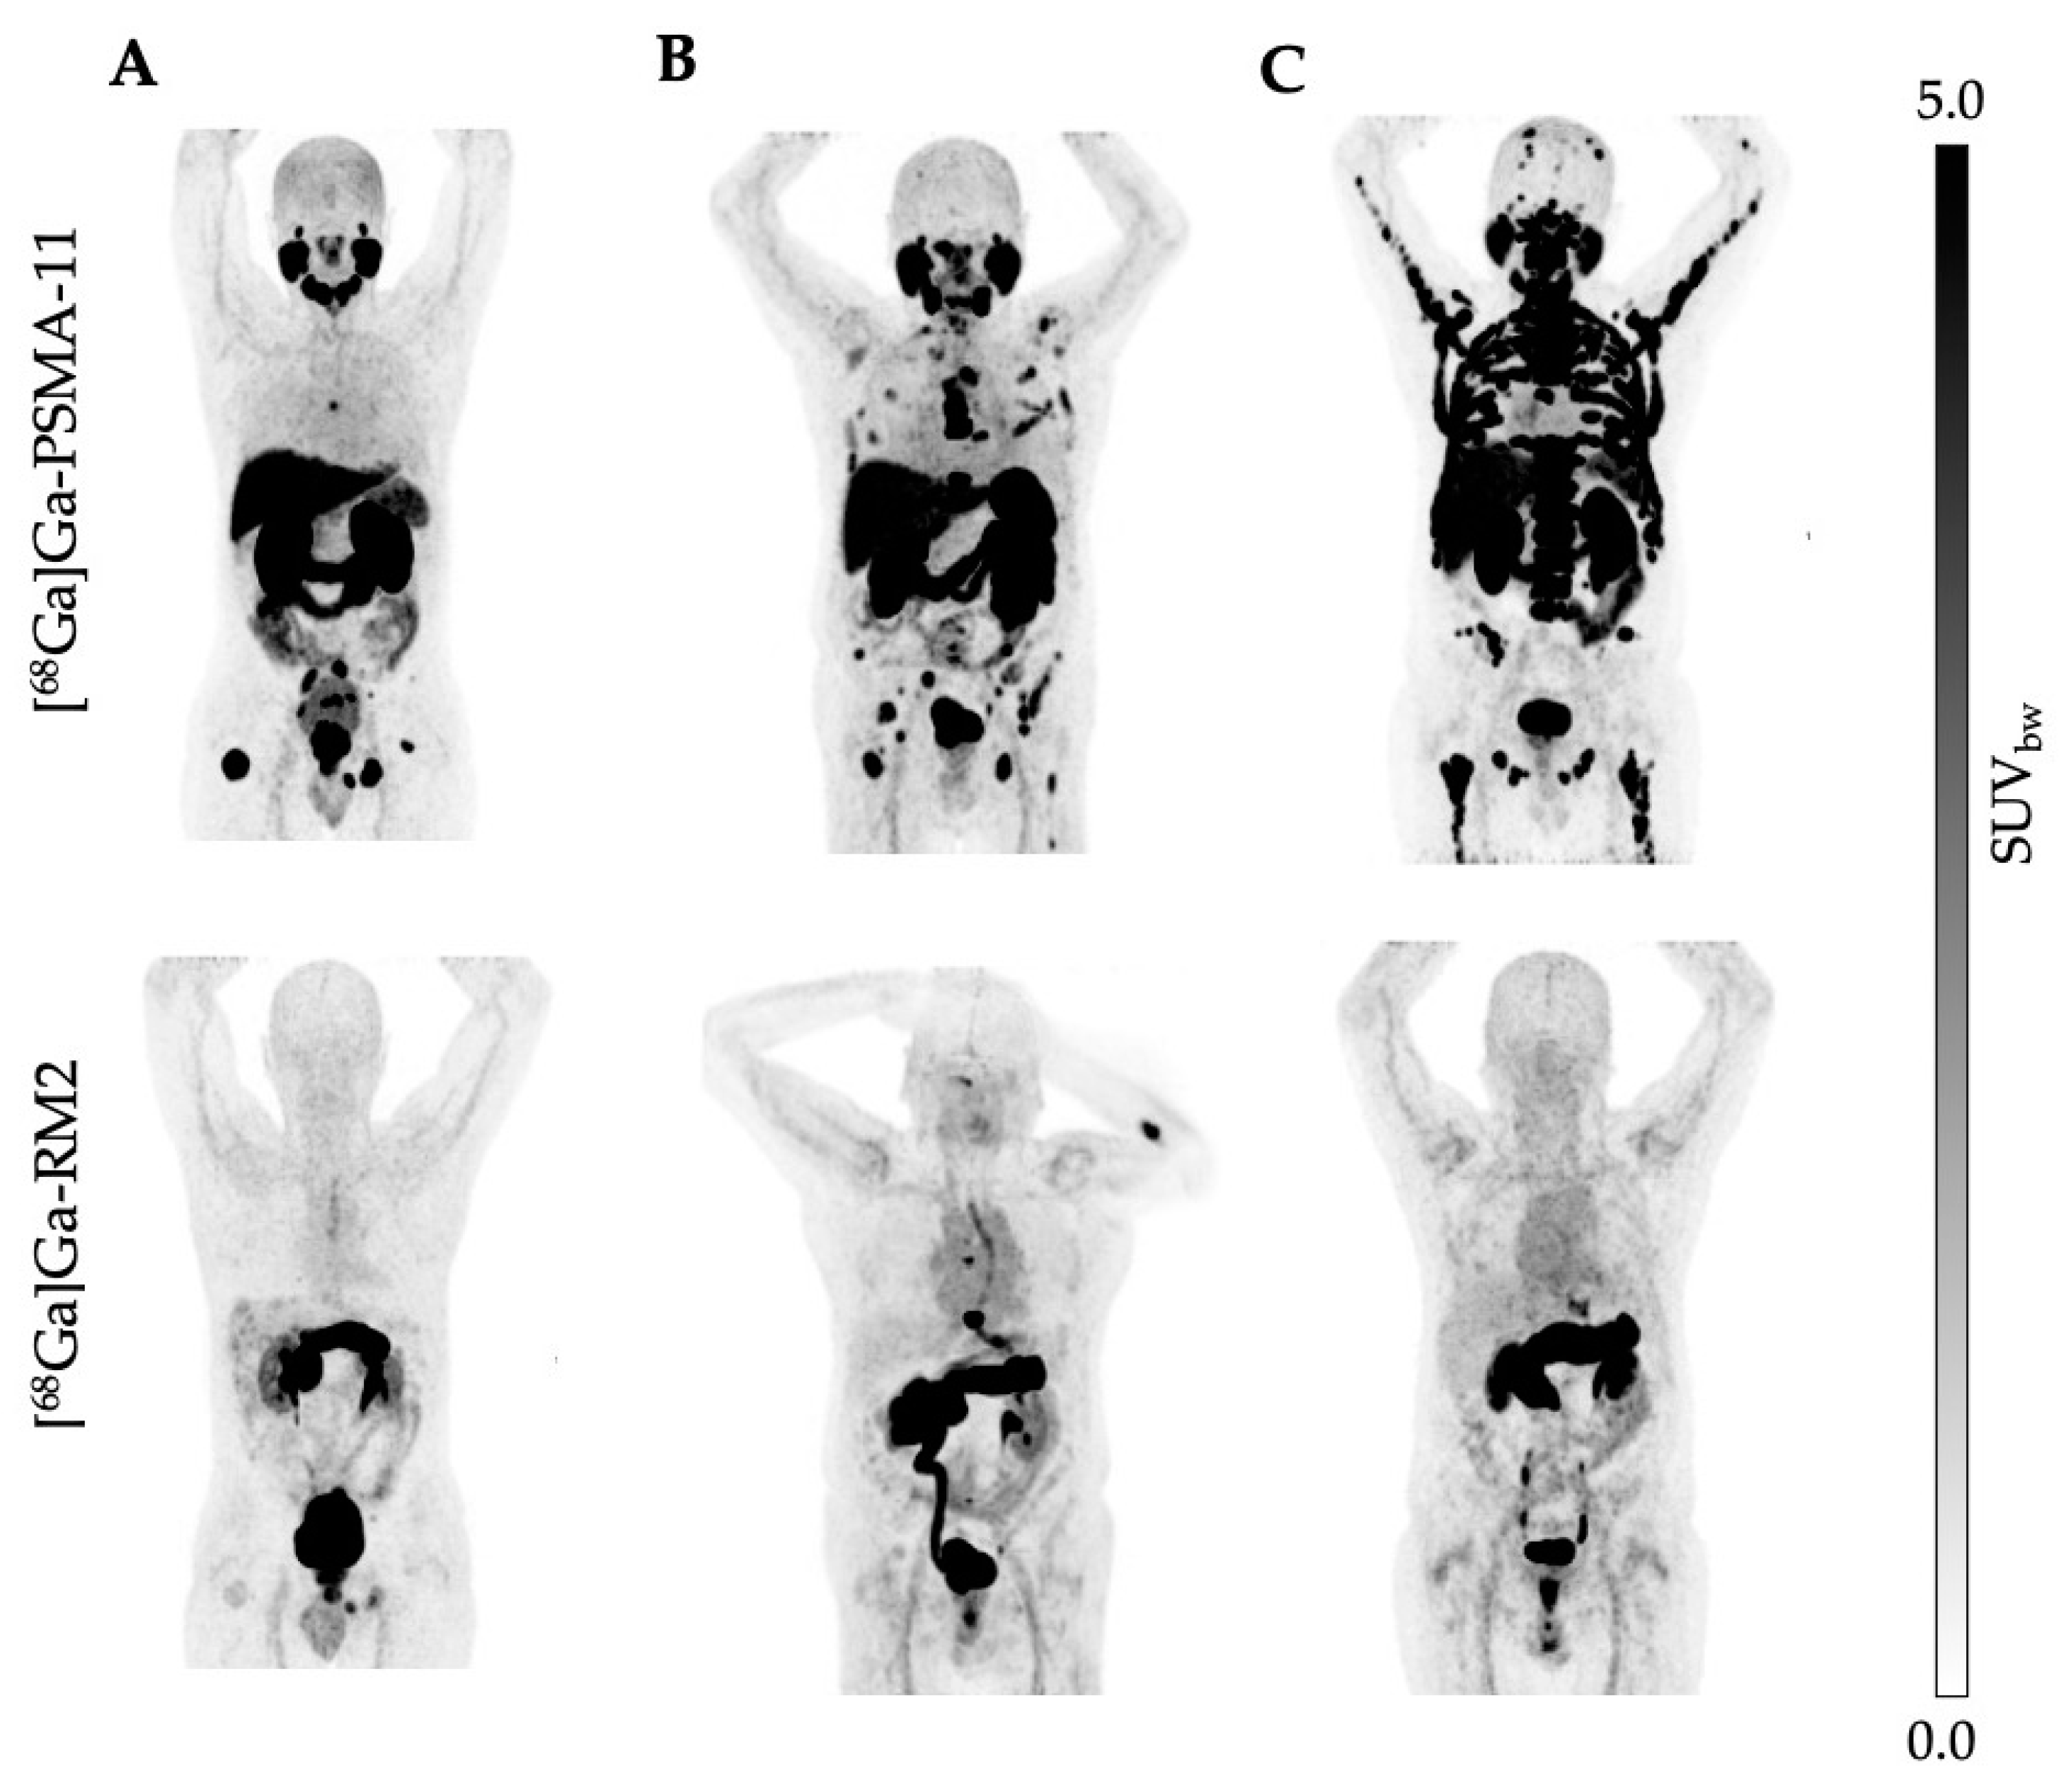

3.2. Uptake Comparison between [68Ga]Ga-PSMA-11 and [68Ga]Ga-RM2